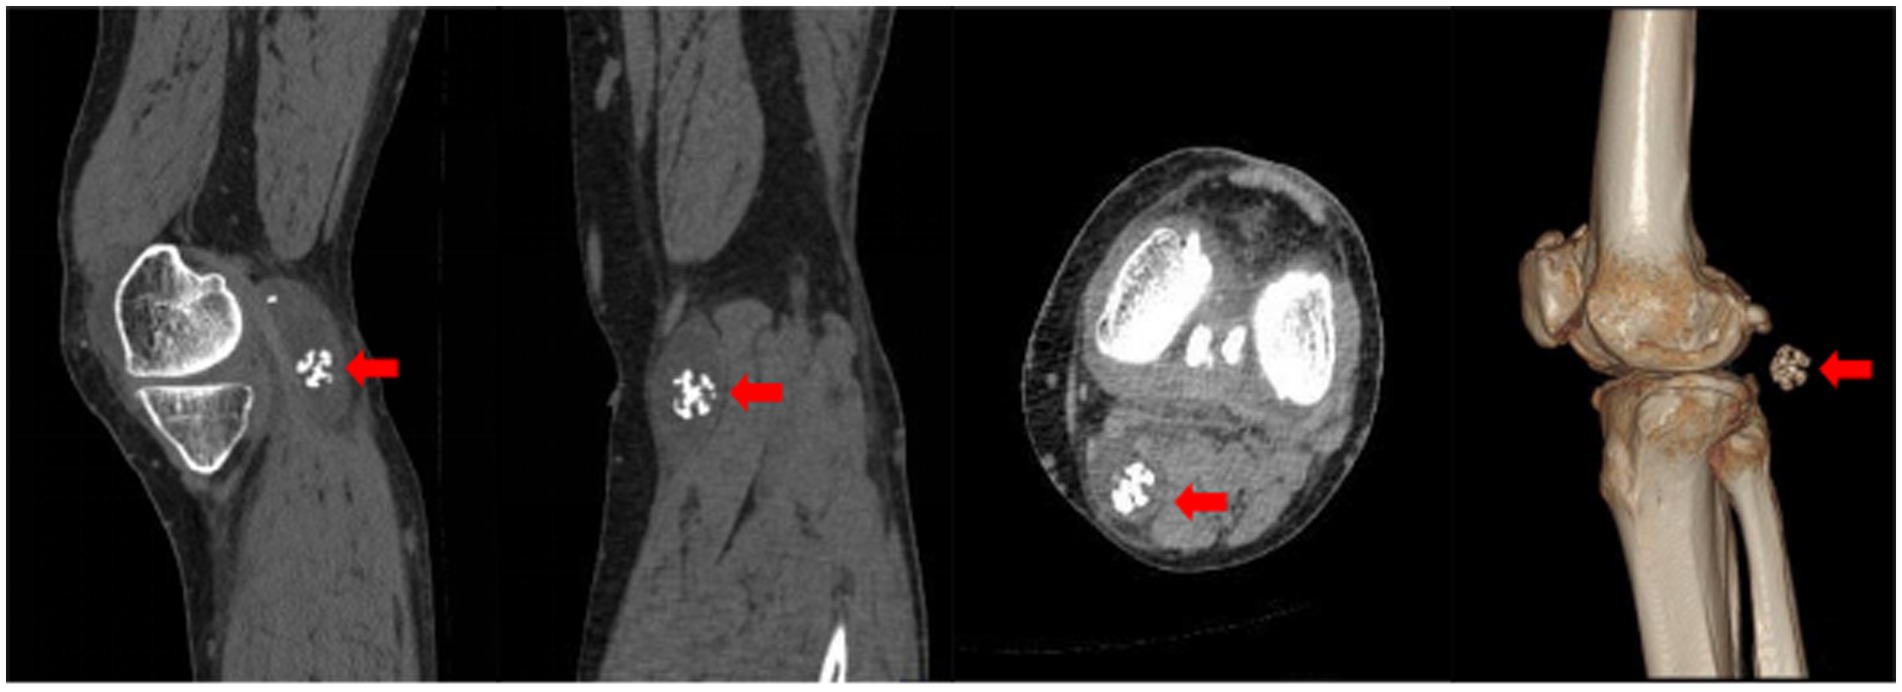

CT scans revealed that the intercondylar eminences of both tibias and the upper margins of the patellas appeared sharpened. Osteophytes were observed at the lower ends of the femurs and the upper ends of the tibias, accompanied by significant narrowing of the joint spaces in both knees. Effusions were noted in the suprapatellar bursae of both knees, with a more pronounced presence in the left knee. An oval-shaped hypodense cystic lesion measuring approximately 60 mm × 25 mm was identified in the popliteal fossa of the left knee, containing multiple nodular masses; the largest of these had a diameter of about 20 mm and resembled a spherical coral (Figure 2).

Figure 2. Axial CT image of the knee. The red arrow highlights the spherical coral-like synovial chondroma within the hypodense popliteal cyst.

Furthermore, the CT slice DICOM data were imported into Mimics 21.0 software for 3D reconstruction, which revealed four nodular hyperdense masses of varying sizes within the hypodense cystic lesion in the popliteal fossa, with the largest mass also resembling a spherical coral (Figure 3).

X-ray is a commonly used imaging method for diagnosing synovial chondromatosis. In lateral knee X-rays, notable calcification or ossified loose bodies can be observed, which is particularly important for diagnosing patients in Milgram stage III. In this study, the patient’s X-ray images exhibited calcified nodules resembling spherical coral. However, X-ray examinations have difficulty distinguishing synovial chondromatosis from other soft tissue tumors, and there is also uncertainty in diagnosing popliteal cysts. Therefore, further CT and MRI examinations are necessary. CT, through three-dimensional reconstruction, can clearly display the number, location, size, and morphological characteristics of loose bodies. For joint effusion and early knee joint lesions, MRI, with its superior soft tissue signal resolution, can effectively illustrate the degree of synovial hyperplasia, the size of popliteal cysts, and the morphology of intra-capsular loose bodies. These imaging findings provide precise data for determining the number and positional relationships of tumors, offering critical references for the complete intraoperative removal of lesions and reducing the postoperative recurrence rate (15).